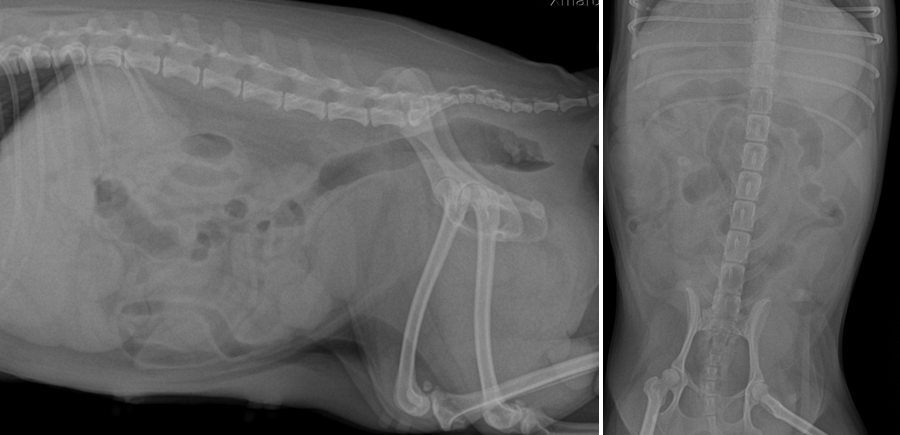

검사요크셔테리어 강아지 자궁축농증수술 I 부평 프라임 동물병원 ▶ 방사선 검사 환자의 정확한 상태를 확인하기 위해 화상검사를 실시하였습니다.

영상 검사를 통해 확장된 자궁이 관찰되었고, 이것은 자궁 축농증이라고 진단되었습니다.